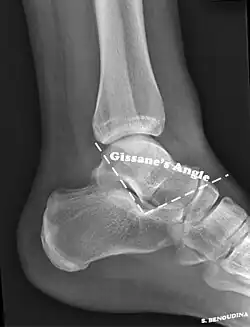

The Angle of Gissane, or "Critical Angle", is the angle formed by the downward and upward slopes of the calcaneal superior surface. On a lateral radiograph, an angle of Gissane > 130° suggests fracture of the posterior subtalar joint surface. Böhler's angle, or the "Tuber Angle", is another normal anatomic landmark seen in lateral radiographs. It is formed by the intersection of 1) a line from the highest point of the posterior articular facet to the highest point of the posterior tuberosity, and 2) a line from the former to the highest point on the anterior articular facet. Böhler's angle is normally 25° to 40°.[14] It is named after Austrian physician Lorenz Böhler.[16] A decreased angle is indicative of a calcaneal fracture.